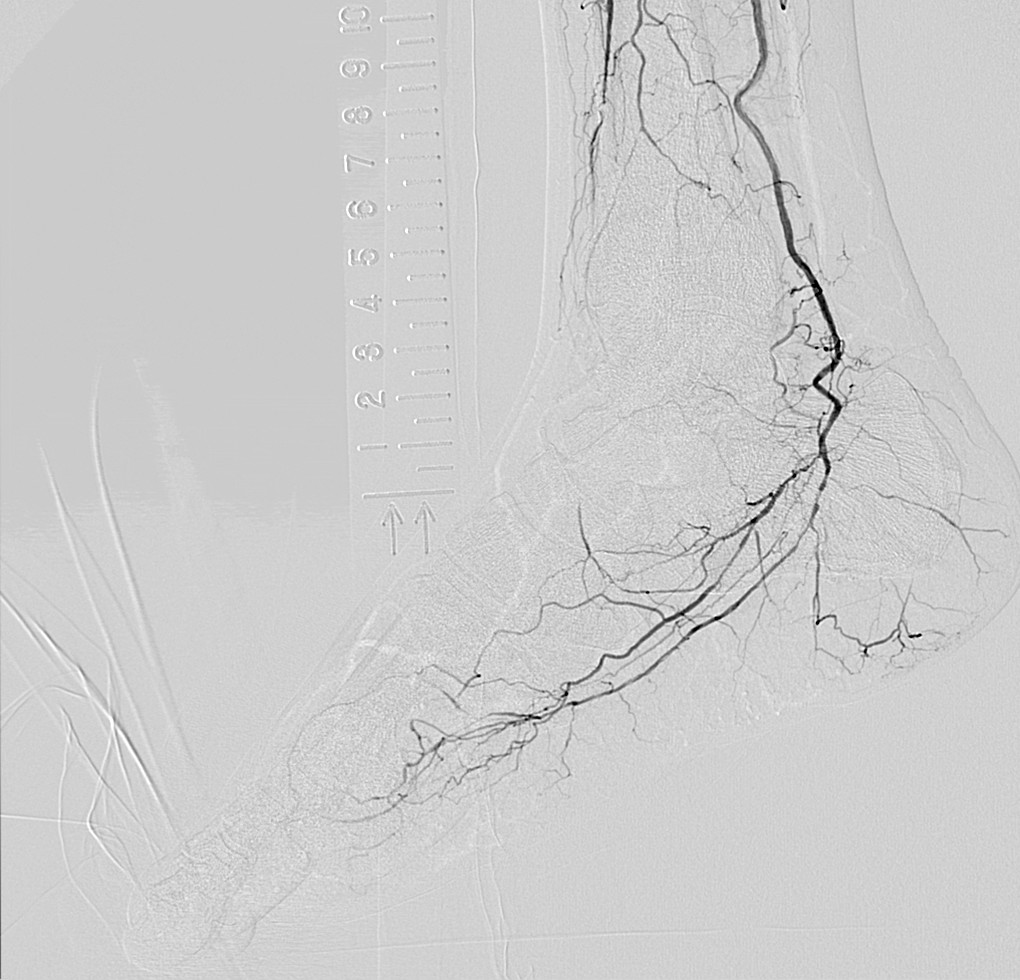

- 首先,双腿能拍到同一画面中这一点很好。还有手术中,由于能够区别使用纵向16英寸、横向16英寸,例如,希望拍摄双腿全长时可以横着跟踪拍摄。采用DSA时,由于迄今为止也都不得不分几次进行拍摄,因此需要患者承担造影剂的负担,而我认为拍摄次数减少对于患者来说是大有裨益的。但即便如此,如果不能拍摄冠状动脉就没有意义了,然而这台机器对于冠状动脉也可以正常拍摄。在搭桥等过程中,无需跟踪也可以将希望看到的区域全部拍摄出来,因此画面不会发生抖动,容易拍摄。

另外,正如曾我医生所说的那样,在跟踪拍摄时,通过将16英寸一侧置于横向,可以一次拍摄到双下肢的全部长度,导管床也在纵向的移动行程长,仅通过移动导管床就可以拍摄到足尖的位置。

- SCORE Chase真的很不错。即使导管床横向移动也能将血管图像自动连接起来,真是非常厉害。为什么之前没有呢?所有来云顶国际医院参观的人都觉得很震惊。

- 大家都说“这个真好啊”。一直以来都是通过手动的方式将血管的图像连接起来的,由于图像间有亮度差,因此非常费功夫。多亏有了SCORE Chase,不需要再这样做了。它会对图像进行校正,瞬间将图像自动连接起来,真的非常方便。

- 即使对于患者细微的动作、震动,都会自动进行抖动补偿处理,因此血管的边缘等变得更加清晰。

- 是的。的确非常好。图像会随时自动抖动补偿,显示出没有失准的清晰的DSA,所以我都认为成是理所当然的事情了。丝毫没有不适感,感觉适合用于末梢血管的拍摄。